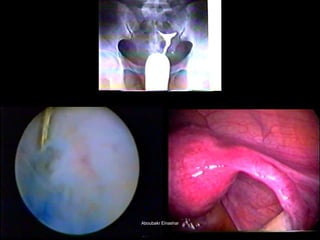

The document discusses the history and development of hysteroscopy. It began in 1869 but did not achieve routine use until improvements to optics, distension media, lighting and instruments in the 1970s-1990s allowed for office procedures without anesthesia. Today, many hysteroscopic procedures have replaced older, more invasive techniques. The document then provides details on rigid and flexible hysteroscopes, lighting sources, distension media, and diagnostic and operative uses of hysteroscopy for conditions like abnormal bleeding, infertility, uterine anomalies and assisted conception. Contraindications are also outlined.